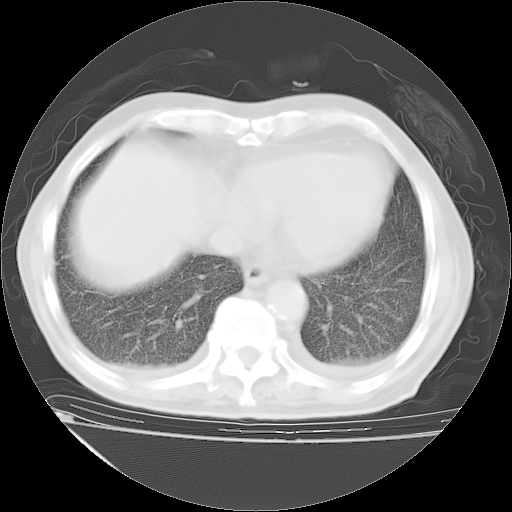

补充下:5月9日胸部CT:似乎已见双下肺胸腔积液了,鉴于目前有下肢水肿,肝功示:白蛋白低,应注意多浆膜腔积液(漏出液可能大?),需注意!

甲强龙80mg/日+抗结核治疗(异烟肼+利福霉素+乙胺丁醇)10天。复查肺部CT。

治疗10天肺部CT